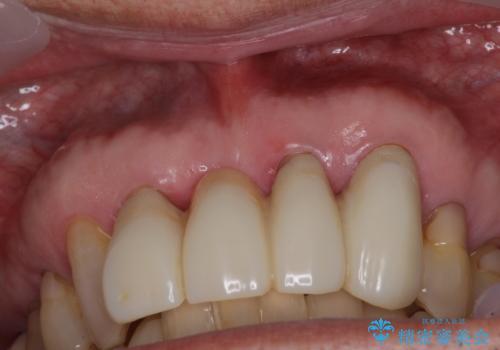

上の歯は見た目を良くしたいというご希望があったため、歯周外科処置を行った歯についてはセラミッククラウンで補綴することとしました。

気になっていた歯の痛みや歯肉からの出血がなくなり、改善したいと思っていた外見も綺麗に仕上がり、大変満足していただきました。